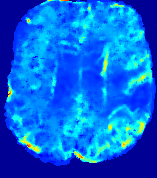

LesionRefer to captionRefer to captionRefer to captionRefer to captionRefer to captionRefer to caption𝐕rgbsubscript𝐕𝑟𝑔𝑏{\bf{V}}_{rgb}Refer to captionRefer to captionRefer to captionRefer to captionRefer to captionRefer to caption𝐕2subscriptnorm𝐕2{\|\bf{V}}\|_{2}Refer to captionRefer to captionRefer to captionRefer to captionRefer to captionRefer to captionRefer to caption3.53.53.52.82.82.82.12.12.11.41.41.40.70.70.70.00.00.0(mm/s)𝑚𝑚𝑠(mm/s)D𝐷DRefer to captionRefer to captionRefer to captionRefer to captionRefer to captionRefer to captionRefer to caption0.0200.0200.0200.0160.0160.0160.0120.0120.0120.0080.0080.0080.0040.0040.0040.0000.0000.000(mm2/s)𝑚superscript𝑚2𝑠(mm^{2}/s)Slice #1Slice #2Slice #3Slice #4Slice #5Slice #6

Figure 3: PIANO feature maps for one stroke patient, where the lesion is located in the left hemisphere. Top row: segmented stroke lesion region (white) on different slices, obtained from ISLES 2017. The corresponding slices for the PIANO feature maps are shown in the following rows.

For a better insight into an estimated velocity field 𝐕𝐕{\bf{V}} and diffusion field 𝐃𝐃{\bf{D}}, we compute the following maps: (1) 𝐕rgbsubscript𝐕𝑟𝑔𝑏{\bf{V}}_{rgb}: Color-coded orientation map of 𝐕=(Vx,Vy,Vz)T𝐕superscriptsuperscript𝑉𝑥superscript𝑉𝑦superscript𝑉𝑧𝑇{\bf{V}}=(V^{x},V^{y},V^{z})^{T}, obtained by normalizing 𝐕𝐕{\bf{V}} to unit length and mapping its 3 components to red, green, blue respectively; (2) 𝐕2subscriptnorm𝐕2\|{\bf{V}}\|_{2}: 222 norm of 𝐕𝐕{\bf{V}}; (3) D𝐷D: scalar field in Eq. 5.

Fig. 3 and Fig. 4 show the PIANO feature maps estimated from two ISLES 2017 patients: all are highly consistent with the lesion in both cases. Details of the blood flow trajectories are revealed in 𝐕rgbsubscript𝐕𝑟𝑔𝑏{\bf{V}}_{rgb} by the ridged patterns and the sharp changes of colors in the unaffected (right) hemisphere, while the flat patterns appearing within the lesion provide little directional information about the velocity and indicate low velocity magnitudes. Velocity magnitudes are more directly visualized via 𝐕2subscriptnorm𝐕2\|{\bf{V}}\|_{2}, from which one can easily locate the lesion where 𝐕2subscriptnorm𝐕2\|{\bf{V}}\|_{2} is low. D𝐷D also indicates lower diffusion values in the lesion, though with less contrast potentially due to the fact that it captures the accumulated effect of CA diffusion at the voxel-level.